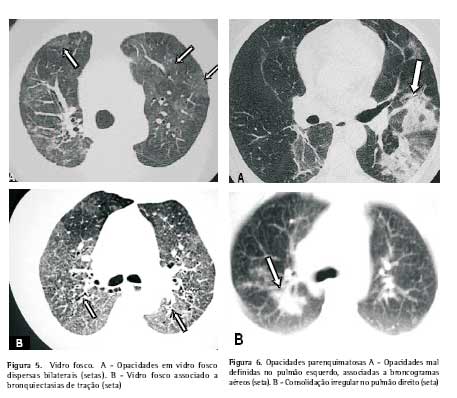

Opacidades em vidro fosco. Este padrão pode ser observado em 14 % a 83 % dos pacientes, tendendo a uma distribuição esparsa. Pode ocorrer isoladamente ou associado a sinais de fibrose pulmonar (Figura 5)(11-13).

Opacidades parenquimatosas. São menos freqüentes que as opacidades em vidro fosco e geralmente surgem no estágio inicial da doença. Localizam-se ao longo dos feixes peribroncovasculares ou na periferia pulmonar. Suas margens são irregulares, sendo freqüente a associação com broncogramas aéreos e nódulos no parênquima adjacente (Figuras 6 e 7)(14).